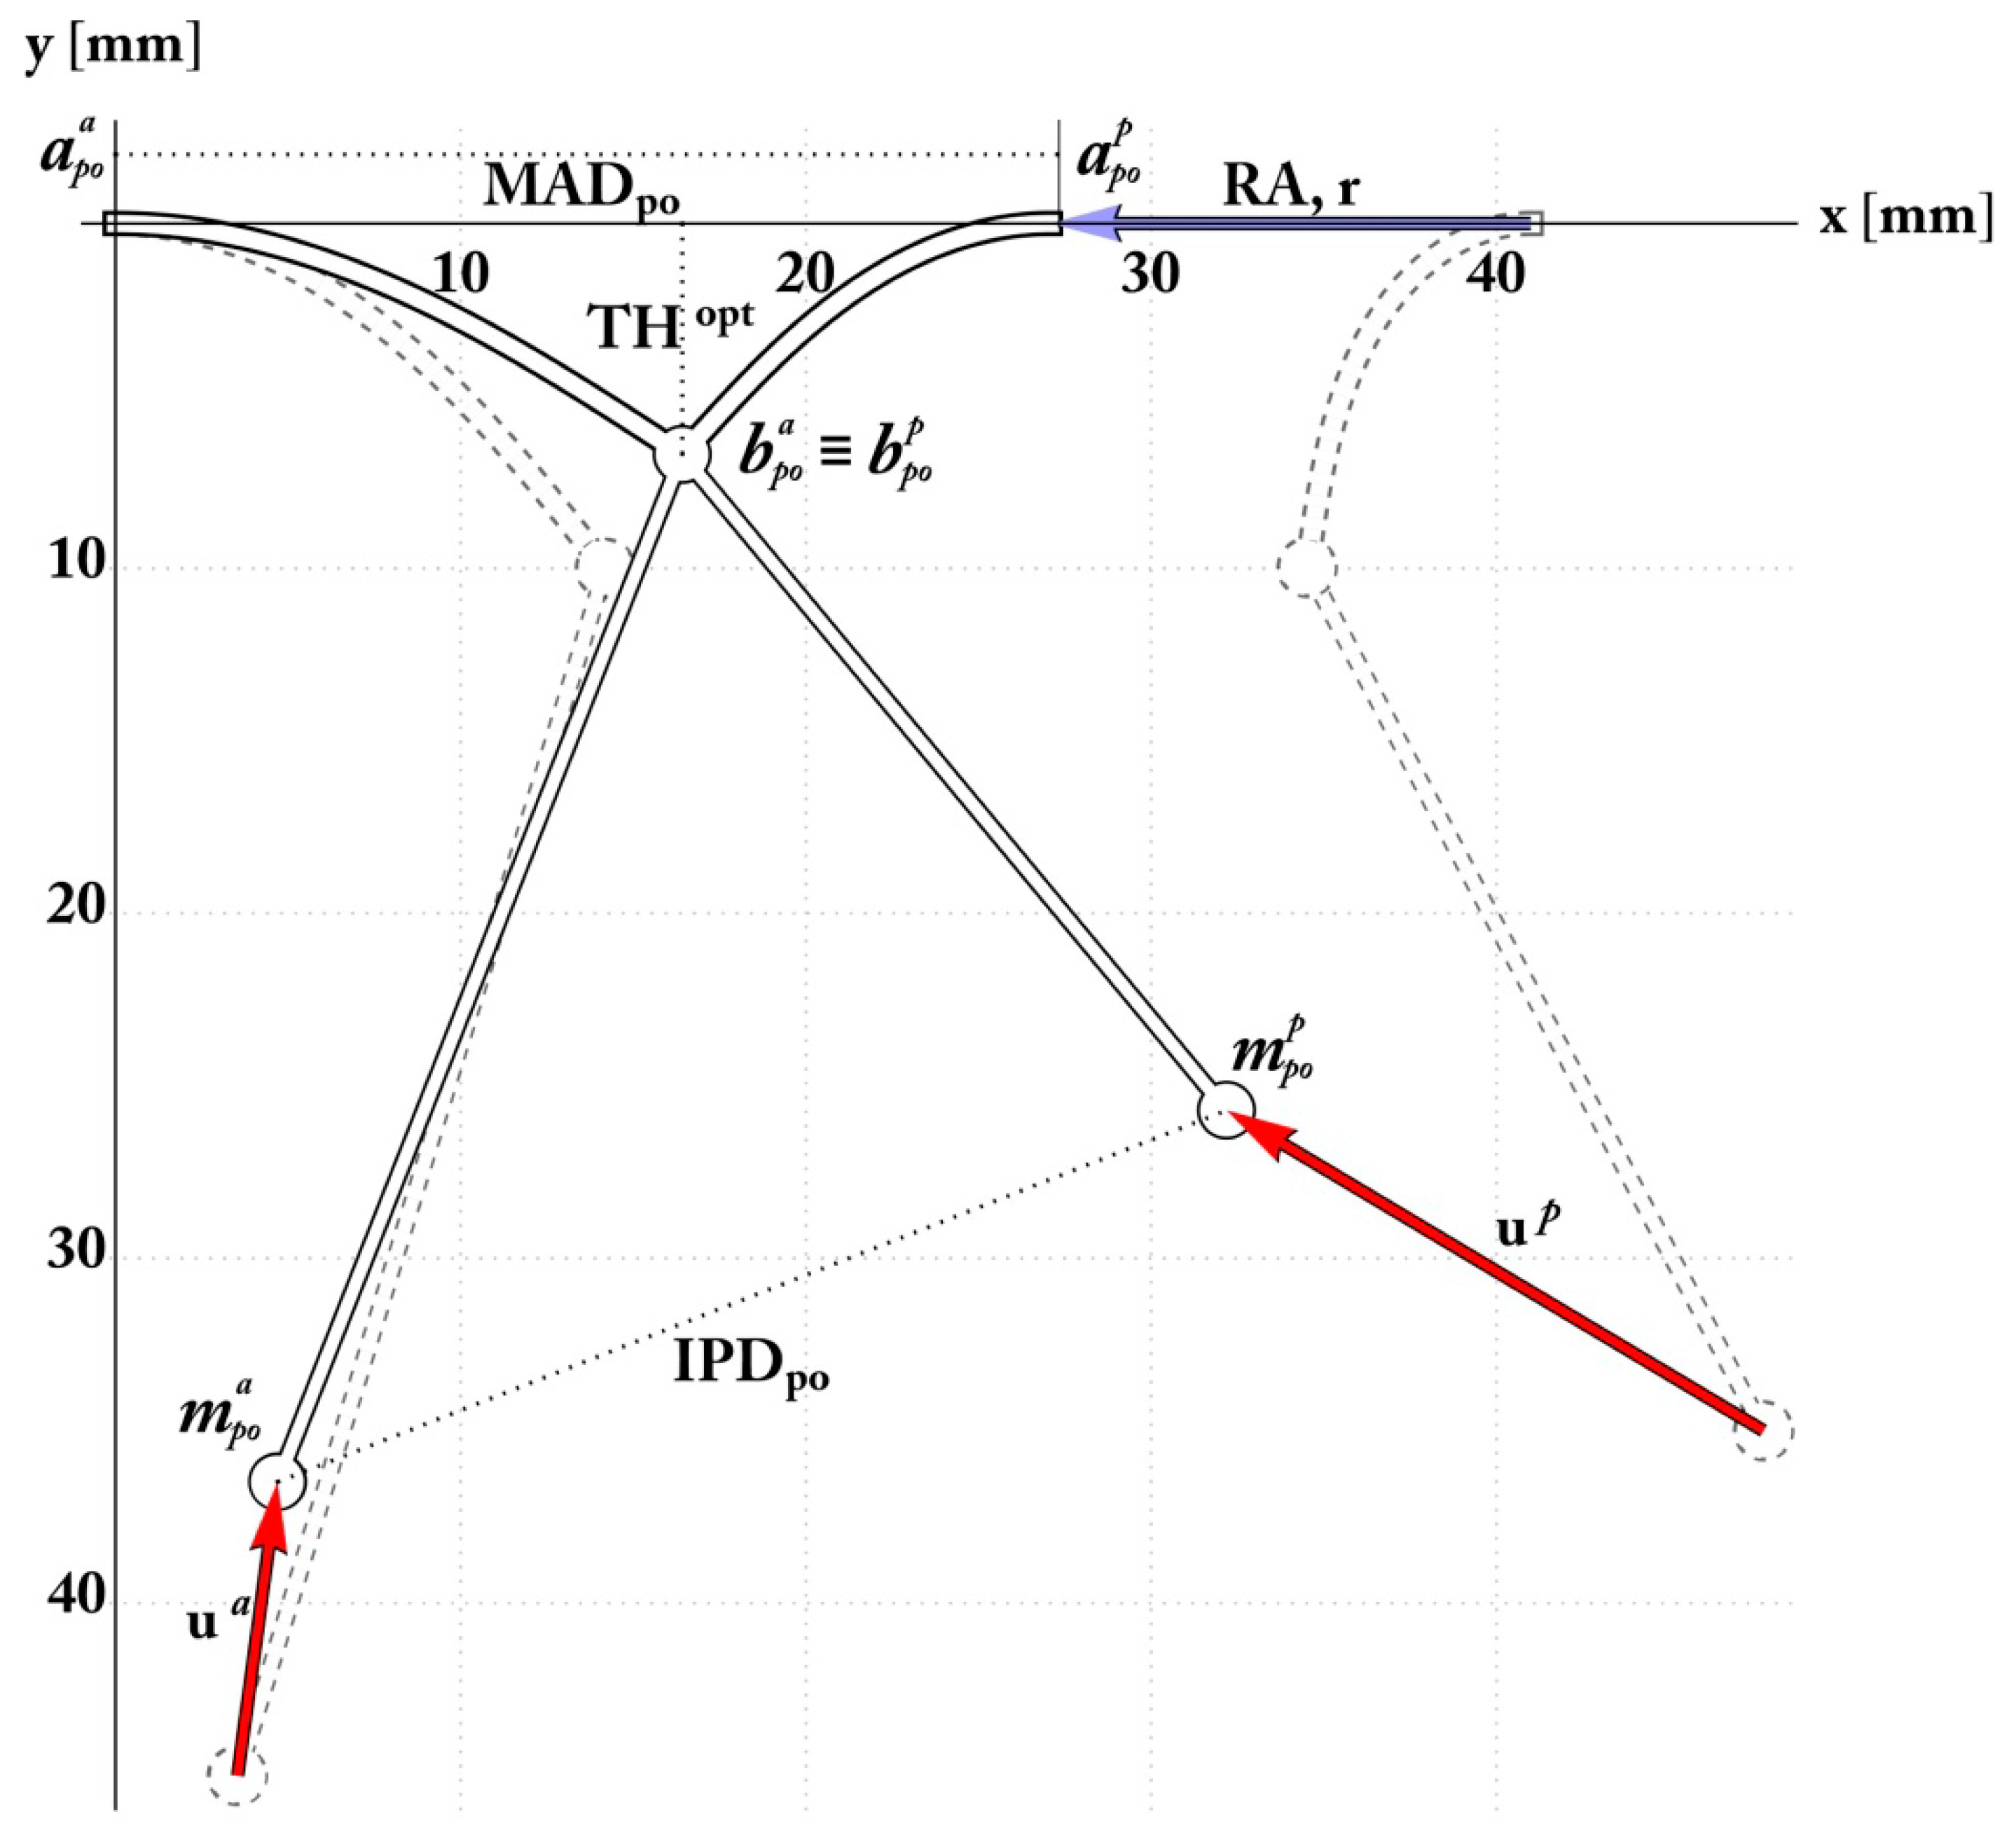

The Pre-Operative Configuration

2.4. Simulation and Optimization of RA and PMA